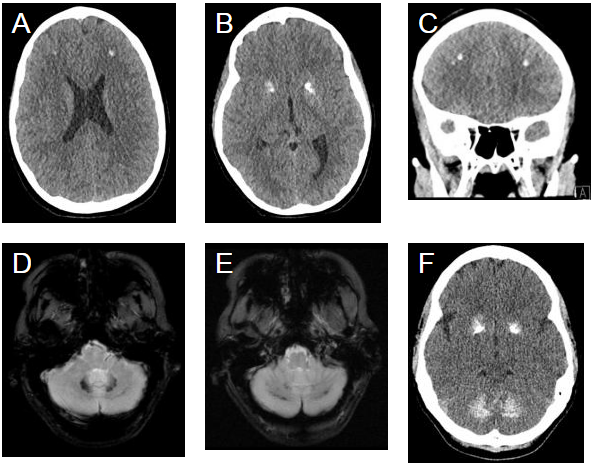

图1 A-C:患者CT图像 D-F:患者母亲MRI和CT。(额叶白质(A和C)和苍白球(B)呈高度衰减病灶,齿状核(D)和小脑半球(E)的T2WI上提示低信号,而基底神经节和齿状核(F)呈高度衰减。)

在本病例中,患者有癫痫

病史。然而,2年前做过的一次核磁共振成像并提示钙化,CT上看到的钙化。生化检测显示血清钙、甲状旁腺激素、铁和镁水平正常。进一步的病史显示有家族史,患者母亲的颅内表现相似,符合PFBC的临床诊断。